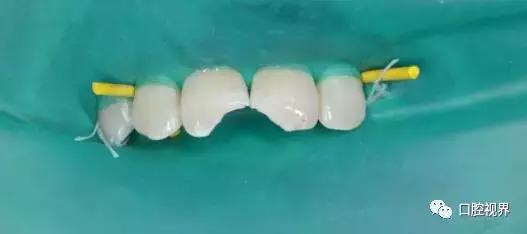

⭐症状:前牙外伤缺损,牙齿咬物崩裂;龋齿,牙齿酸痛,牙齿敏感;牙痛,牙龈根尖区长脓包;牙齿变色

就诊科室:牙体牙髓科,口腔内科

简介:牙齿硬组织的疾病称为牙体病,广义的牙体病也包括牙髓病。 龋病是一种由口腔中多种因素复合作用所导致的牙齿硬组织进行性病损,表现为无机质的脱矿和有机质的分解,随着病程的发展而有一色泽变化到形成实质性病损的演变过程。